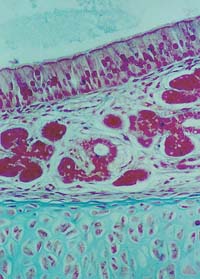

In a pseudostratified epithelium,

all cells rest on a basement membrane.